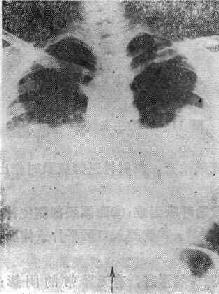

(一)中央型肺水肿 以两肺门为中心向两肺野扩展的阴影(可见支气管气影征),由深变淡,肺野边缘、肺尖和肺底清晰,呈“蝶翼状”分布,这是中央型肺水肿典型的X线表现(图114-1)。常见于心脏和尿毒症患者。治疗及时一般很快吸收消失(3天之内);如治疗不及时,肺泡内除渗液外,可以为凝固的纤维蛋白和巨噬细胞所充填。可产生炎性改变。肺水肿可继发感染。

图114-1 心源性肺水肿的X线表现